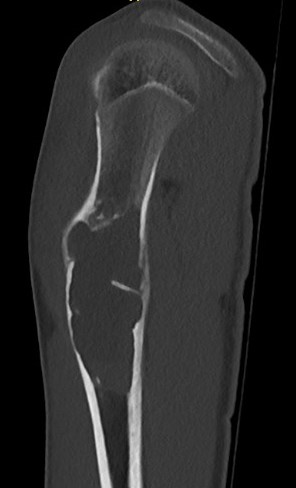

X-ray

Well-defined lucency

- thin sclerotic rim

- usually central

- thinned cortex with slight expansion

- thin internal septa

- can be multi-loculated

Fallen-Leaf (AKA fallen-fragment)

- with pathological fracture

- indicates that the lesion has no matrix and is fluid filled

Fallen leaf sign